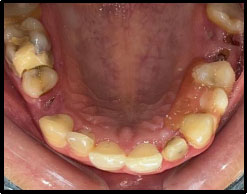

A 34-year-old female patient presented to the Department of Prosthodontics and Crown & Bridge at Santosh Dental College and Hospital, Ghaziabad, following a traumatic fall. Her chief complaint was a fractured maxillary anterior tooth accompanied by compromised facial esthetics. The patient had no previous restorative or endodontic treatment on the affected tooth and maintained satisfactory oral hygiene. Clinical examination revealed no evidence of pain, swelling, or associated soft-tissue pathology. Intraoral evaluation identified an Ellis Class III fracture involving the maxillary left lateral incisor (tooth 22), as illustrated in Fig. (1). Radiographic assessment revealed loss of tooth structure involving the enamel and dentin with pulpal involvement. Pulp vitality testing further confirmed that the tooth was non-vital. The traumatic incident was isolated, and this clinical context guided our decision to use a conservative, adhesive fiber post-and-core system to preserve residual tooth structure.

PRE-operative.

Peeso reamers (sizes 1 and 2) were used for post-space preparation, making sure that 3–4 mm of gutta-percha was retained at the apex. Next, a dual-cure resin cement was used to lute a prefabricated fiber-reinforced post into the canal (Fig. 3). Once the fiber post was in position (Fig. 4). Composite resin was then used to build up the core (Fig. 5). Occlusal view of the core build-up is shown in Fig. (6). Finally, a highly translucent all-ceramic crown was placed, restoring the tooth’s function and aesthetics in alignment with the surrounding dentition in occlusion (Fig. 7) and Occlusal view (Fig. 8).

Post operative - occlusal view.